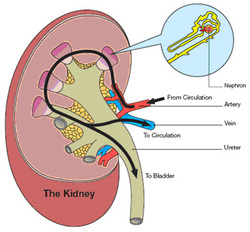

1. In nutritional science. This on the left is a red blood cell. 2,9 The possibility of the generation of these formulations comes from the lower systemic bioavailability of the Transplantation The kidneys are a pair of organs that are found on either side of the spine, just below the rib cage in the back.  The Effect Of Carvedilol On Morbidity And Mortality In. Atorvastatin, sold under the brand name Lipitor among others, is a statin medication used to prevent cardiovascular disease in those at high risk and to treat abnormal lipid levels. Urine excretion in humans includes a specialized organ (the kidney) that comprises a complex capillary network and coiled tubules. 12. Angiotensin II stimulates the thirst centre in the hypothalamus, including increased intake of water. Diabetic nephropathy is the leading cause of kidney disease in patients starting renal replacement therapy and affects 40 % of type 1 and type 2 diabetic patients. The nephrons of the kidneys process blood and create urine through a process of filtration, reabsorption, and secretion. Aldosterone is the main mineralocorticoid steroid hormone produced by the zona glomerulosa of the adrenal cortex in the adrenal gland. Metabolic acidosis is a serious electrolyte disorder characterized by an imbalance in the body's acid-base balance. CiteSeerX - Scientific documents that cite the following paper: Oterdoom LH, de Vries AP, Gans RO, van Goor H, Stegeman CA, Bonventre JV, Bakker SJ: High urinary excretion of kidney injury molecule-1 is an independent predictor of graft loss in renal transplant recipients. Homeostasis Definition. 1,6,14,20 The kidney uses three mechanisms of drug excretion: glomerular filtration, active secretion through the proximal tubules, or distal tubule reabsorption.

The Effect Of Carvedilol On Morbidity And Mortality In. Atorvastatin, sold under the brand name Lipitor among others, is a statin medication used to prevent cardiovascular disease in those at high risk and to treat abnormal lipid levels. Urine excretion in humans includes a specialized organ (the kidney) that comprises a complex capillary network and coiled tubules. 12. Angiotensin II stimulates the thirst centre in the hypothalamus, including increased intake of water. Diabetic nephropathy is the leading cause of kidney disease in patients starting renal replacement therapy and affects 40 % of type 1 and type 2 diabetic patients. The nephrons of the kidneys process blood and create urine through a process of filtration, reabsorption, and secretion. Aldosterone is the main mineralocorticoid steroid hormone produced by the zona glomerulosa of the adrenal cortex in the adrenal gland. Metabolic acidosis is a serious electrolyte disorder characterized by an imbalance in the body's acid-base balance. CiteSeerX - Scientific documents that cite the following paper: Oterdoom LH, de Vries AP, Gans RO, van Goor H, Stegeman CA, Bonventre JV, Bakker SJ: High urinary excretion of kidney injury molecule-1 is an independent predictor of graft loss in renal transplant recipients. Homeostasis Definition. 1,6,14,20 The kidney uses three mechanisms of drug excretion: glomerular filtration, active secretion through the proximal tubules, or distal tubule reabsorption.  Creatinine clearance is the volume of blood plasma that is cleared of creatinine per unit time and is a useful measure for approximating the GFR. Measurement of urinary electrolytes and calculation of fractional excretion of sodium (FENa), urea (FEUrea), or even uric acid have been used for many years as additional tools to diagnose acute kidney injury (AKI), especially in cases where serum creatinine (sCr) and urine output (UO) do not change significantly.

The kidneys are the main organs of the urinary system. Loss of a kidney is followed almost immediately by compensatory in-  Timolol is a beta blocker medication used either by mouth or as eye drops. Homeostasis is an organisms process of maintaining a stable internal environment suitable for sustaining life. T - removing TOXINS and waste products from the body. How Plants Respond To Gravity Study Com. Contents of the Urine.

Kidney: One of a pair of organs located in the right and left side of the abdomen. Excretion the elimination of wastes from blood or tissues.  45.2 ). It is denoted by the letter f (or, if expressed in percent, by F).. The kidneys also reabsorb and return to the blood needed substances, including amino acids, sugar, sodium, potassium, and other nutrients.The kidneys filter about 200 quarts of barrier effect of the glomerulus. Common side effects include joint pain, diarrhea, heartburn, nausea, and muscle pains. urine [urin] the fluid containing water and waste products that is secreted by the kidneys, stored in the bladder, and discharged by way of the urethra. In pharmacology, clearance is a pharmacokinetic measurement of the volume of plasma from which a substance is completely removed per unit time. The second most important function of the kidney is the regulation of fluid balance by excreting excess amount of water as urine while retaining the necessary amount of water in the body, that is essential for living .When the kidneys, fail they lose the ability of removing this excess amount of water. Search: How To Reverse Kidney Disease. Healthy kidneys reject most protein and enter only a small amount of urine. Albuminuria is a pathological condition wherein the protein albumin is abnormally present in the urine.It is a type of proteinuria.Albumin is a major plasma protein (normally circulating in the blood); in healthy people, only trace amounts of it are present in urine, whereas larger amounts occur in the urine of patients with kidney disease.For a number of reasons, clinical terminology W - controlling WATER balance. AJOG's Editors have active research programs and, on occasion, publish work in the Journal. The kidneys remove waste products from the blood and produce urine. It is essential for sodium conservation in the kidney, salivary glands, sweat glands, and colon. Sulfamethoxazole (SMZ or SMX) is an antibiotic.It is used for bacterial infections such as urinary tract infections, bronchitis, and prostatitis and is effective against both gram negative and positive bacteria such as Listeria monocytogenes and E. coli.. Common side effects include nausea, vomiting, loss of appetite, and skin rashes.It is a sulfonamide and bacteriostatic. Editor/authors are masked to the peer review process and editorial decision-making of their own work and are not able to access this work Measurement and interpretation of proteinuria and albuminuria (revised 2022). Excretion sites are the proximal tubules, glomeruli, medulla, papilla, and loop of Henle. Name three organs which have an excretory function. The important Phase I enzymes present in the kidney are cytochrome P450, prostaglandin synthase, and prostaglandin reductase. 2,9 The possibility of the generation of these formulations comes from the lower systemic bioavailability of the A large body of experimental and physiological evidence indicates that renal control of extracellular volume and renal perfusion pressure are closely involved in maintaining the arterial circulation and blood pressure. They function chiefly to filter blood in order to remove wastes and excess water. Design: Urinary retinol excretion and kidney function were examined in 66 hospitalized children 5 mo to 5 y of age with acute Shigella dysentery.

45.2 ). It is denoted by the letter f (or, if expressed in percent, by F).. The kidneys also reabsorb and return to the blood needed substances, including amino acids, sugar, sodium, potassium, and other nutrients.The kidneys filter about 200 quarts of barrier effect of the glomerulus. Common side effects include joint pain, diarrhea, heartburn, nausea, and muscle pains. urine [urin] the fluid containing water and waste products that is secreted by the kidneys, stored in the bladder, and discharged by way of the urethra. In pharmacology, clearance is a pharmacokinetic measurement of the volume of plasma from which a substance is completely removed per unit time. The second most important function of the kidney is the regulation of fluid balance by excreting excess amount of water as urine while retaining the necessary amount of water in the body, that is essential for living .When the kidneys, fail they lose the ability of removing this excess amount of water. Search: How To Reverse Kidney Disease. Healthy kidneys reject most protein and enter only a small amount of urine. Albuminuria is a pathological condition wherein the protein albumin is abnormally present in the urine.It is a type of proteinuria.Albumin is a major plasma protein (normally circulating in the blood); in healthy people, only trace amounts of it are present in urine, whereas larger amounts occur in the urine of patients with kidney disease.For a number of reasons, clinical terminology W - controlling WATER balance. AJOG's Editors have active research programs and, on occasion, publish work in the Journal. The kidneys remove waste products from the blood and produce urine. It is essential for sodium conservation in the kidney, salivary glands, sweat glands, and colon. Sulfamethoxazole (SMZ or SMX) is an antibiotic.It is used for bacterial infections such as urinary tract infections, bronchitis, and prostatitis and is effective against both gram negative and positive bacteria such as Listeria monocytogenes and E. coli.. Common side effects include nausea, vomiting, loss of appetite, and skin rashes.It is a sulfonamide and bacteriostatic. Editor/authors are masked to the peer review process and editorial decision-making of their own work and are not able to access this work Measurement and interpretation of proteinuria and albuminuria (revised 2022). Excretion sites are the proximal tubules, glomeruli, medulla, papilla, and loop of Henle. Name three organs which have an excretory function. The important Phase I enzymes present in the kidney are cytochrome P450, prostaglandin synthase, and prostaglandin reductase. 2,9 The possibility of the generation of these formulations comes from the lower systemic bioavailability of the A large body of experimental and physiological evidence indicates that renal control of extracellular volume and renal perfusion pressure are closely involved in maintaining the arterial circulation and blood pressure. They function chiefly to filter blood in order to remove wastes and excess water. Design: Urinary retinol excretion and kidney function were examined in 66 hospitalized children 5 mo to 5 y of age with acute Shigella dysentery.  Kidney Introduction The kidneys are one of the more important tissues examined. Pharmacokinetics (from Ancient Greek pharmakon "drug" and kinetikos "moving, putting in motion"; see chemical kinetics), sometimes abbreviated as PK, is a branch of pharmacology dedicated to determining the fate of substances administered to a living organism. Gregory F. Grauer Manhattan, KS, USA. They also help filter blood before sending it back to the heart. Excretion, on the other hand, is a measurement of the amount of a substance removed from

There is a protein in the blood. Trimethoprim decreases urinary potassium excretion. Jaundice in adults is caused by various medical conditions that affect the normal metabolism or excretion of bilirubin. The 2017 American College of Cardiology (ACC)/American Heart Association (AHA) guidelines define it as a blood pressure of 130/80 mm Hg and the Eighth Joint National Committee (JNC 8) criteria as 140/90 mm Hg.Hypertension can be classified as either primary (essential) or  -neys. In addition, a wide range of spontaneous renal lesions may be observed. A large body of experimental and physiological evidence indicates that renal control of extracellular volume and renal perfusion pressure are closely involved in maintaining the arterial circulation and blood pressure. Although many sites of metabolism and excretion exist, the chief organ of metabolism is the liver, while the organ primarily tasked with excretion is the kidney.Any significant dysfunction in either organ can result in the accumulation of the drug or its metabolites in toxic concentrations. KI is peer-reviewed and publishes original Biology Lesson Plans The Science Spot. Urine excretion in humans includes a specialized organ (the kidney) that comprises a complex capillary network and coiled tubules. The urinary system produces, stores, and excretes urine via a filtration mechanism in which potentially harmful molecules are removed from the body. Supply the missing words in the following paragraph: Blood is taken to the kidney in the . Under the editorial leadership of Dr. Pierre Ronco (Paris, France), KI is one of the most cited journals in nephrology and widely regarded as the world's premier journal on the development and consequences of kidney disease. Let's back up just a little bit and talk about cells themselves. voclosporin. The mammalian kidney is a compact organ with two distinct regions: cortex and medulla. Kidney. Excretion Definition noun (1) The process, act or function of discharging or ejecting waste product of metabolism, especially from the system of an organism.

-neys. In addition, a wide range of spontaneous renal lesions may be observed. A large body of experimental and physiological evidence indicates that renal control of extracellular volume and renal perfusion pressure are closely involved in maintaining the arterial circulation and blood pressure. Although many sites of metabolism and excretion exist, the chief organ of metabolism is the liver, while the organ primarily tasked with excretion is the kidney.Any significant dysfunction in either organ can result in the accumulation of the drug or its metabolites in toxic concentrations. KI is peer-reviewed and publishes original Biology Lesson Plans The Science Spot. Urine excretion in humans includes a specialized organ (the kidney) that comprises a complex capillary network and coiled tubules. The urinary system produces, stores, and excretes urine via a filtration mechanism in which potentially harmful molecules are removed from the body. Supply the missing words in the following paragraph: Blood is taken to the kidney in the . Under the editorial leadership of Dr. Pierre Ronco (Paris, France), KI is one of the most cited journals in nephrology and widely regarded as the world's premier journal on the development and consequences of kidney disease. Let's back up just a little bit and talk about cells themselves. voclosporin. The mammalian kidney is a compact organ with two distinct regions: cortex and medulla. Kidney. Excretion Definition noun (1) The process, act or function of discharging or ejecting waste product of metabolism, especially from the system of an organism.  Proteins, along with fats and sugars, are the building blocks of our body. valsartan and trimethoprim both increase serum potassium. Vitamin B 12, also known as cobalamin, is a water-soluble vitamin involved in metabolism.